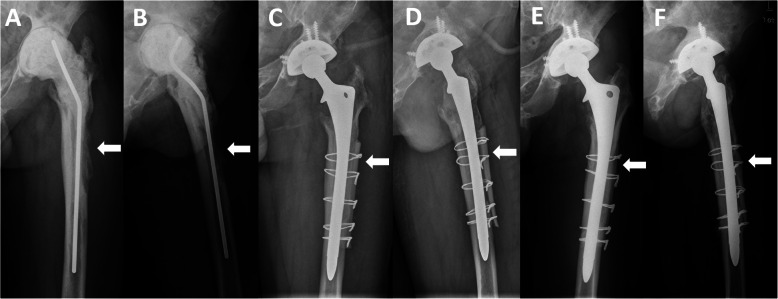

Fig. 3.

Radiographs of a 44-year-old man who underwent revision THA for periprosthetic joint infection. a, b Anteroposterior and lateral radiographs prior to stage 2 revision THA showing a Paprosky type IIIA femoral bone defect. c, d Radiographs immediately after revision THA using an extensively porous-coated stem with cortical strut allografts, showing that the cortical strut allografts bridged the bone defects (white arrow) and supported the thinning cortex. e, f Postoperative radiographs at 9 years showing successful incorporation of the cortical strut allografts to the host bone, bone restoration in the bone defect area (white arrow), and a significant increase in femoral width. No sign of stress shielding and distal cortical hypertrophy was observed. The stem was assessed as bone ingrowth stable

Patients with cortical strut allografts had more osseous restoration in bone defect area than patients without allografts (63.8% vs 30.7%, P < 0.001) (Table 2, Figs. 2 and 3). Osseous restoration was positively associated with ETO (Pearson chi-square test, P = 0.014). The occurrence of distal cortical hypertrophy showed no difference between the allografts group and no allografts group (29.8% and 38.7%, respectively) (Fig. 1). Femoral width was significantly higher in femurs with allografts than in femurs without allografts at the immediate postoperative stage and latest follow-up (both P < 0.001). Compared to the preoperative width, the femoral width at the latest follow-up increased by a mean of 6.9 mm (21.8% of preoperative width) in the allografts group, while the femoral width decreased by 1.1 mm in the no allografts group at the latest follow-up.